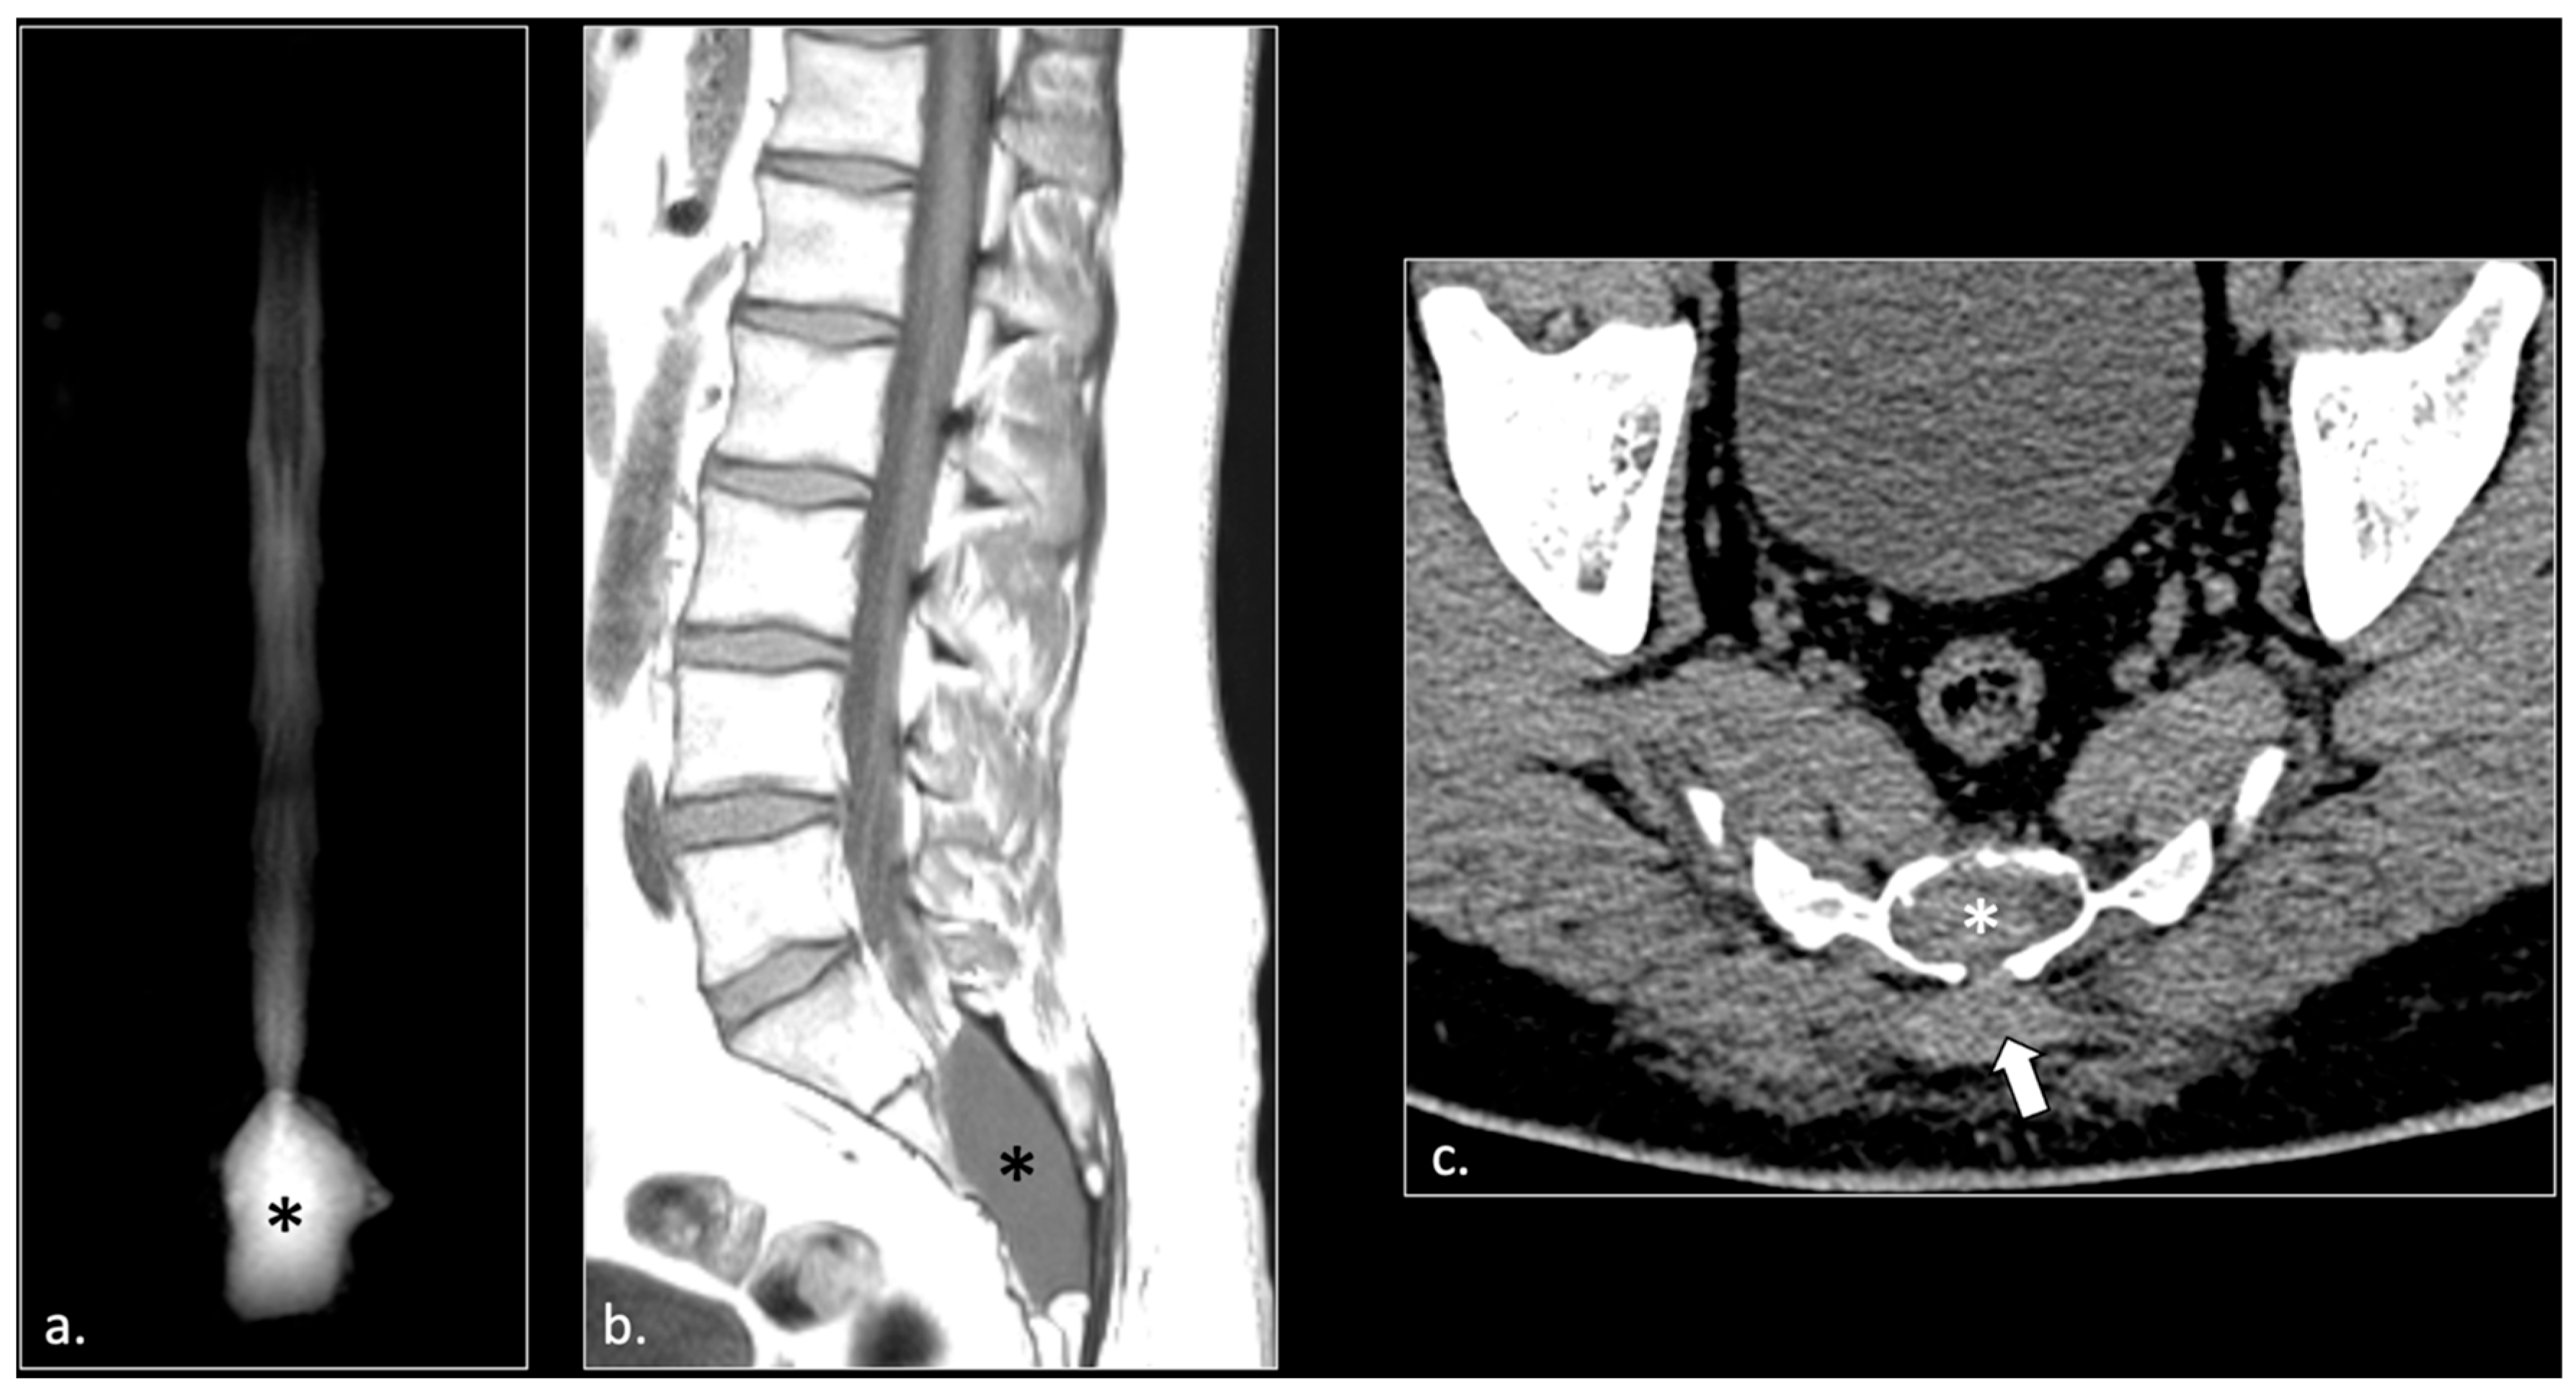

- Hemorrhagic Tarlov’s cyst of the sacrum (1 patient);

- Giant cyst of the prostatic utricle (1 patient);